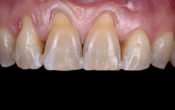

Fig. 03 : au niveau endobucale, une malocclusion de classe 2 division 1 avec supraclusion marquée, un surplomb de 4 mm et une dysharmonie dento-maxillaire.

Fig. 09 : vues endobuccales de fin de traitement.